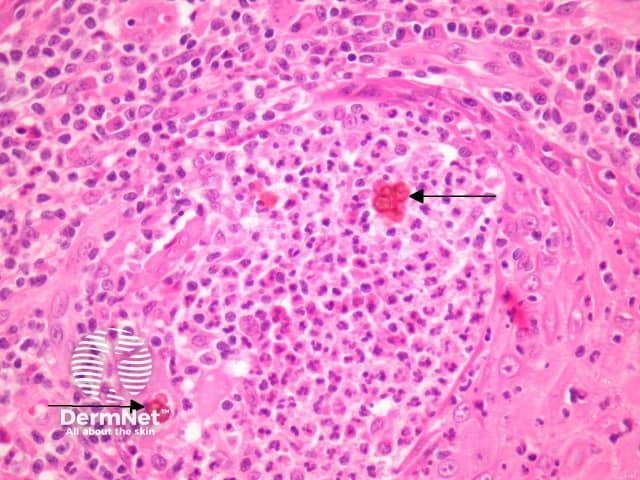

Histopathology of chromoblastomycosis may show typical thick-walled dark-brown 'sclerotic' cells on skin biopsy confirming the presence of a dematiaceous fungus. It is dark coloured due to melanin in the walls of the organism.

Figure 4